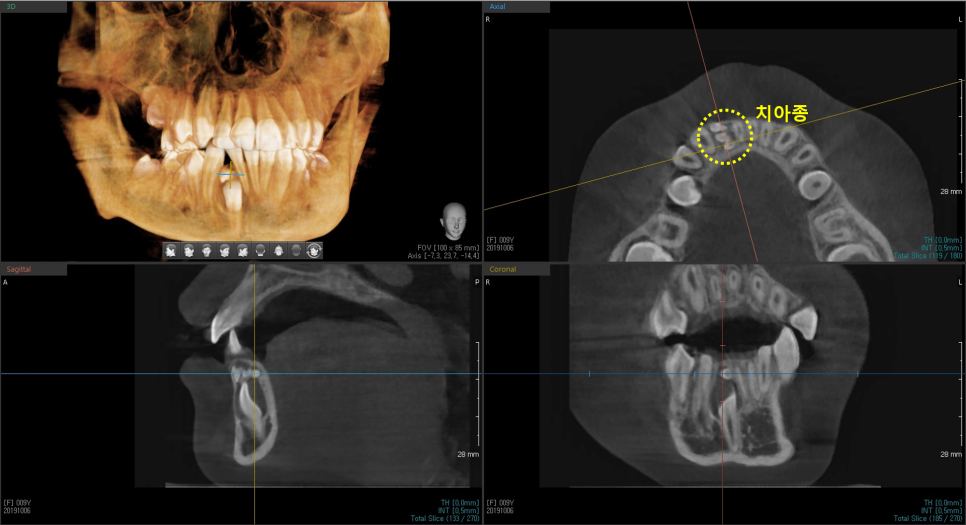

방사선 촬영 결과, 아래 오른쪽 두번째 앞니가 매복되어 잇몸 안쪽 깊숙이 자리 잡고 있었고, 상방에는 치아종이 가로 막고 있었습니다.

7f829c6152fc0f266ad641c0f7ec26e1_1763089930_3017.png

판교교정치과 / 치료 전 파노라마 엑스레이

7f829c6152fc0f266ad641c0f7ec26e1_1763089951_2483.png

판교교정치과 / 치료 전 Cone Beam CT

(치아종이 무엇인지 궁금하신 분들은 지난 포스팅을 참고해주세요.)

매복치 상방을 가로 막고 있던 치아종은 제거했습니다.